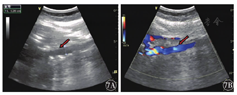

患者2女性,53岁。因"腹部持续性隐痛,阵发性加重,偶有腰背部疼痛,发热2 d"于2018年11月16日入院。入院当天行彩色多普勒超声检查发现下腔静脉近段血流充盈缺损,管腔内可见一规则、边缘整齐、高回声的实质性、漂浮条索状物,狭窄率为60%~70%,长约6.0 cm,上缘距右心房约3.0 cm。右肾静脉内无血流显示(图5)。由于此漂浮物较长,距右心房距离较近,无法行下腔静脉滤器置入术,于2018年11月26日全麻下行右肾切除术+下腔静脉瘤栓切除术,术中剖腹探查发现右肾静脉内无血流充盈,可扪及实性质韧肿物由肾实质内延伸至下腔静脉内,沿右肾静脉根部剖开下腔静脉壁,见静脉内黄色光滑质韧瘤栓,呈漂浮样与静脉无粘连,予以取出(图6)。术后患者生命体征平稳。术后病理诊断:右肾血管平滑肌脂肪瘤。患者术后行彩色多普勒超声检查,提示下腔静脉内管壁光滑,管腔内径正常,血流通畅,充盈良好(图7)。患者于2018年12月5日出院。